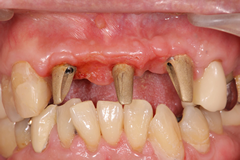

<治療前>

上顎前歯部が崩壊して残すことが出来ない状態になっている。